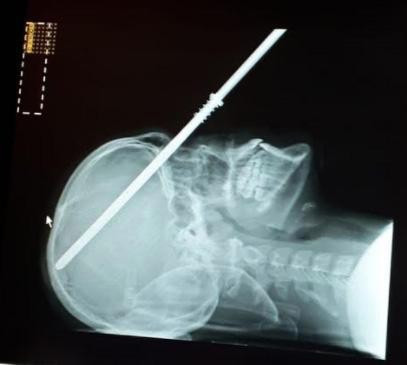

| Vì không bị tổn thương não, White vẫn có thể hồi phục lại thị lực của mình. |